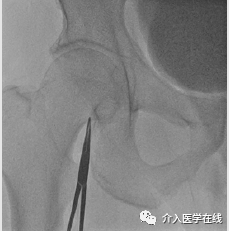

6. 将 0.018”导丝穿过针头放置如图3所示,0.018”导丝容易进入股动脉或髂动脉的小分支,增加了穿孔的风险。因此,在透视引导下推进 0.018" 导丝非常重要。

图3